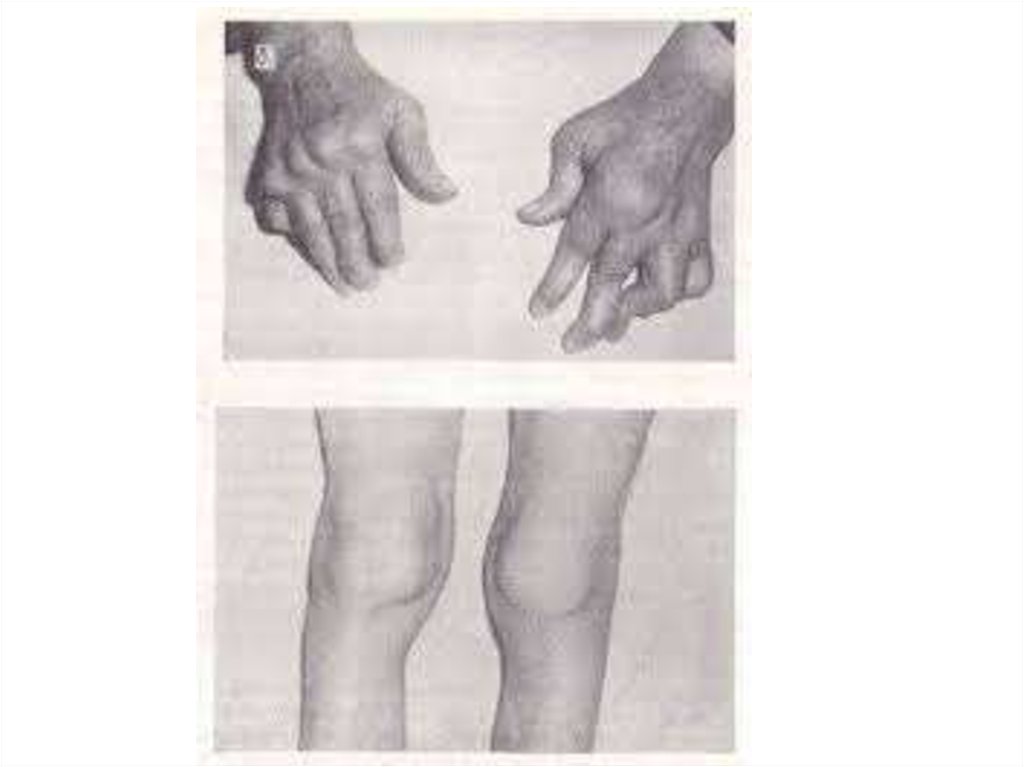

Симптомы и признаки туберкулеза: как распознать заболевание

Раздел: Визуальные уроки